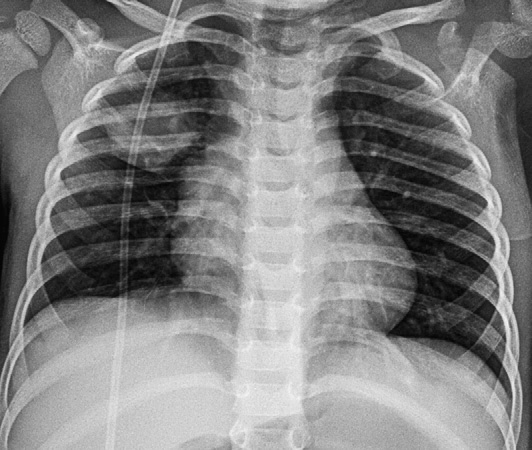

Обследование проводится в прямой и боковой проекциях грудной клетки, с прицельной съёмкой подозрительных участков, а при необходимости — в косых проекциях, в режиме обзорной рентгенографии для выявления прямых признаков очаговой пневмонии. Цель обследования — выявление рентгенологических сигналов воспалительных инфильтратов, оценка характера, локализации и распространённости очагового уплотнения лёгочной ткани, а также состояния прилежащих структур.

Рентгенография выявляет следующие признаки очаговой пневмонии:

Наличие одного или нескольких очагов уплотнения лёгочной ткани диаметром 1–2 см с нечёткими контурами, сигнализирующих о воспалительном инфильтрате в пределах ацинуса или дольки.

Сливные инфильтраты с тенденцией к формированию более крупных участков затемнения, преимущественно в сегментах нижней или средней доли.

Усиление и деформация лёгочного рисунка в зоне поражения за счёт перибронхиального воспаления и отёка межальвеолярных перегородок.

Сохранённые или частично прослеживаемые бронхиальные просветы (воздушные бронхограммы) на фоне инфильтративных изменений.

В отдельных случаях — утолщение плевры или незначительное количество пристеночного выпота на стороне воспалительного процесса.